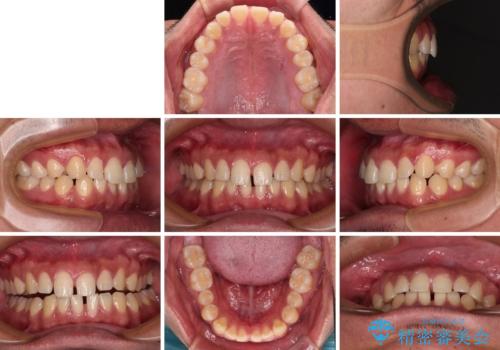

- 上下前歯の隙間を気にして来院された患者様です。

飲み込みや話をするときに舌を突出させる癖が強くあり、それが原因でスペースが空いていました。

舌癖を改善するためのトレーニングを行いながら、ワイヤー装置を用いて前歯の隙間を閉じていくこととしました。

舌のトレーニングをしっかりと行ってくださったおかげで、順調に治療を終えることができました。

舌の突出癖が速やかに改善され、後戻りによるスペースは今のところ認められておりません。